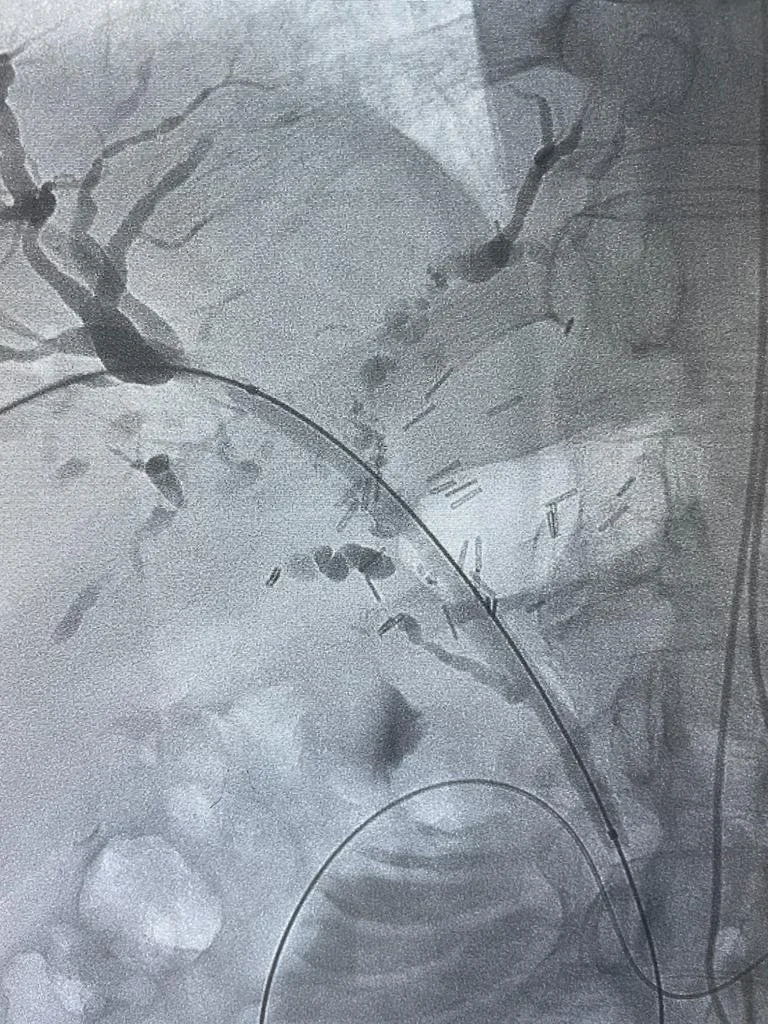

Drenaje biliar con coledocolitiasis

Colangiograma percutaneo y drenaje biliar.

La colangiografía transhepática percutánea es un abordaje que se utiliza para examinar los conductos biliares. En este procedimiento, se introduce una aguja a través de la piel y el hígado para acceder a los conductos biliares, y se inyecta un medio de contraste para visualizarlos en una radiografía. Este abordaje se realiza bajo anestesia local y sedación consciente, y se puede utilizar tanto para diagnóstico como para tratamiento. En algunos casos es necesario realizar el drenaje biliar percutáneo a través de la misma aguja utilizada en la colangiografía. En este caso, se inserta un catéter a través de la aguja para drenar la bilis y aliviar la obstrucción de los conductos biliares. La colangiografía transhepática percutánea se utiliza para diagnosticar y tratar diversas enfermedades de los conductos biliares, como cálculos biliares y tumores.